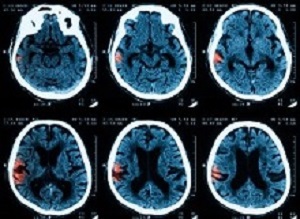

For the latest trial, people who were diagnosed as having had bleeding on the brain – confirmed by CT scan – were offered the chance to take part in the study. Where the person was too ill to decide, permission was asked of their family or close friends. Where no family were available a doctor unconnected with the study decided if the patient should take part.

CT scans of the patients' brains were performed 24 hours after their stroke and their progress was monitored and measured at day two and day seven after their stroke. The final follow-up was performed at 90 days.